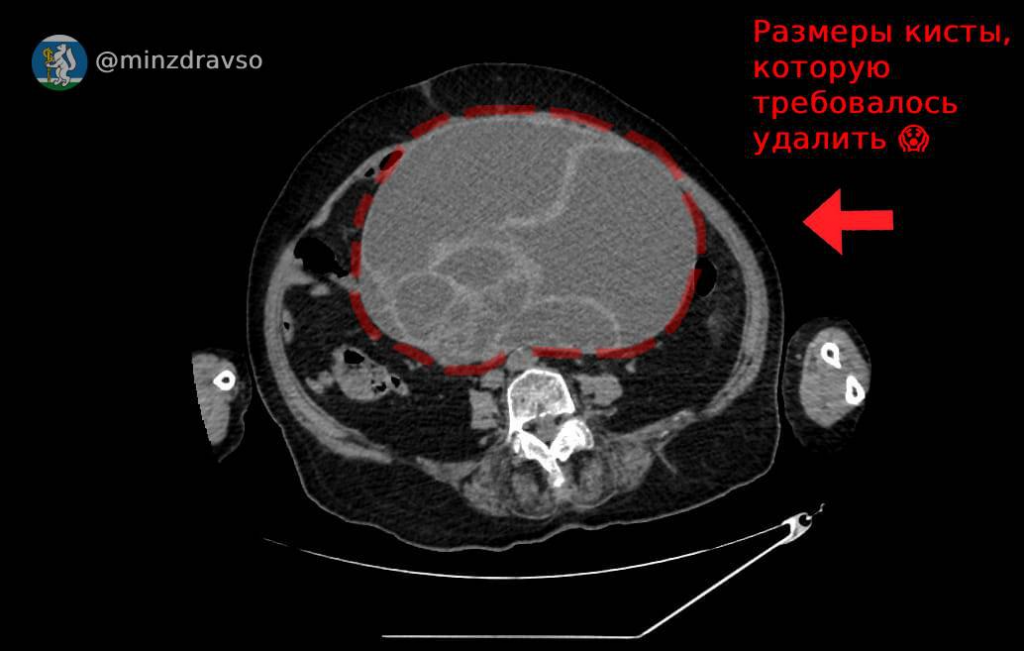

Пожилая женщина поступила в приёмное отделение Красноуфимской районной больницы в тяжёлом состоянии: давление упало до критических цифр, была выраженная одышка, сильная боль в животе, отсутствовали стул и мочеиспускание. Пациентку госпитализировали в палату интенсивной терапии, стабилизировали её состояние и провели обследование. Компьютерная томография выявила в брюшной полости новообразование размером 32х25х22 сантиметра и весом 4,5 килограмма, которое перекрутилось на основании и сдавило все внутренние органы.

«Кисты такого размера, к счастью, встречаются очень редко. Главная опасность для пациента кроется именно в размере: образование оказывает давление на внутренние органы и нарушает их работу. Кроме этого, при перекруте кисты, как в случае нашей пациентки, начинается некроз тканей, а это может привести к перитониту», — пояснил заведующий отделением акушерства и гинекологии Красноуфимской РБ Юрий Шахурин.